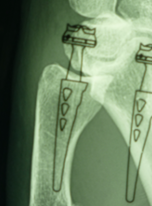

Preparations for the surgery can begin well in advance of the actual procedure. The portal is created in the patient’s hand, then the radiographs are analysed to determine the location of the arthritis and how the implant will work. Selection of the right size by using x-rays with the same scale than the x-ray templates. Assessing the positioning of a Maia implant, with the stem closely following the curve of the metacarpal, running along the lateral cortex is shown in figures 8 and 9. Centred on the trapezium, the x-ray confirms that the trapezium will allow for implantation of the cup.

There are other types of implant, with single or dual mobility designs, usually designed for a cementless fit. It is hard to rank the different implants, and all series with 5 to 10 years FU report satisfactory outcomes for the designs currently on the market. Nevertheless, for dual mobility implants it is perhaps too early yet to determine their place. Supporters of dual mobility highlight the low rate of dislocation and lesser PE wear, whereas those who prefer single mobility designs argue with survivorship well beyond 10 years (17 years in one personal series using an ISIS™ implant).